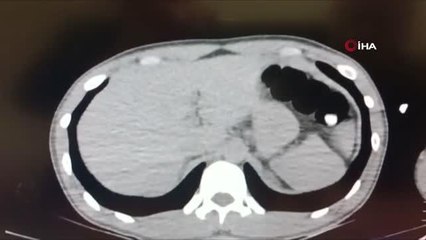

Zanlının bağırsak filmibr -Filmde bağırsaklarında yabancı cismin belli olmasıbr -Bağırsaklarından çıkanların görüntüsübr -Zanlının emniyetten çıkartılmasıbr -Adliyeye götürülmesibrbr( ADANA ) Bağırsağından 47 paket uyuşturucu çıktı "haberim yok" dedi- Adana'da yakalanan İran uyruklu bir şahsın çekilen tomografisinde bağırsağında 47 paket uyuşturucu olduğu tespit edilip ilaç yöntemiyle 5 gün sonra çıkarıldı- Bağırsağından 116 gram metanfetamin, 104 gram eroin ve 107 gram afyon sakızı çıkan zanlının "Van'da beni uyutmuşlardı o zaman koymuş olmalılar haberim yok" dediği öğrenildi ADANA br br - Adana'da yakalanan İran uyruklu bir şahsın çekilen tomografisinde bağırsağında 47 paket uyuşturucu olduğu tespit edilip ilaç yöntemiyle 5 gün sonra çıkarıldı. Zanlınını, "Van'da beni uyutmuşlardı o zaman koymuş olmalılar haberim yok" demesi dikkat çekti. Adana ve Van Emniyet Müdürlüğü Narkotik Suçlarla Mücadele Şube Müdürlüğü ekiplerinin ortak çalışmasında, İran'dan Van üzerinden Türkiye'ye giriş yapan ve uçakla Adana'ya giden Faramarz Tayefehrostami (52) isimli İran uyruklu şahsın uyuşturucu sevkıyatı yaptığı bilgisine ulaşıldı. Bunun üzerine Adana polisi havalimanında zanlıyı beklemeye başladı.br Van-Adana uçağı havalimanına iniş yapınca zanlı polis tarafından gözaltına alındı. Zanlı emniyete getirilerek sorguya alındı. Polis yaptığı bagaj ve üst aramasında uyuşturucuya rastlamadı. Bunun üzerine polis zanlının uyuşturucu yutma yöntemiyle taşıyacağını düşünerek zanlıya bu yöntemi kullanıp kullanmadığını sordu ancak zanlı bunu inkar etti. Polis bunun üzerine savcılıktan alınan izinle zanlıyı Çukurova Üniversitesi Tıp Fakültesi Balcalı Hastanesi Gastroenteroloji Bölümüne götürdü. Burada zanlının bağırsak tomografisi çekildi. Zanlının bağırsaklarında serçe parmağı büyüklüğünde yabancı cisimler olduğu tespit edildi. Buna rağmen zanlı uyuşturucu olmadığını ileri sürmeye devam etti. Doktorlar zanlıya özel bir ilaç vererek bağırsaklarında yabancı cisimlerin tuvalet yoluyla çıkmasını sağladı. 5 günün sonunda zanlının bağırsaklarından 4 pakette 116 gram metamfetamin, 21 pakette 104 gram eroin, 22 pakette 107 gram afyon sakızı çıktı. Zanlının uyuşturucular çıktıktan sonra ifade değiştirip, "Van'da beni uyutmuşlardı o zaman koymuş olabilirler ne yaptıklarını bilmiyorum benim haberim yok" dediği öğrenildi. Zanlı ifadesi alındıktan sonra adliyeye sevk edildi. Adana'da 21 Aralık 2019 günü de yine havalimanında, Van'dan gelen İran uyruklu Seddigh Raşhıdıtavana (58) isimli şahsın bağırsaklarından 49 pakette 765 gram eroin çıkmıştı.